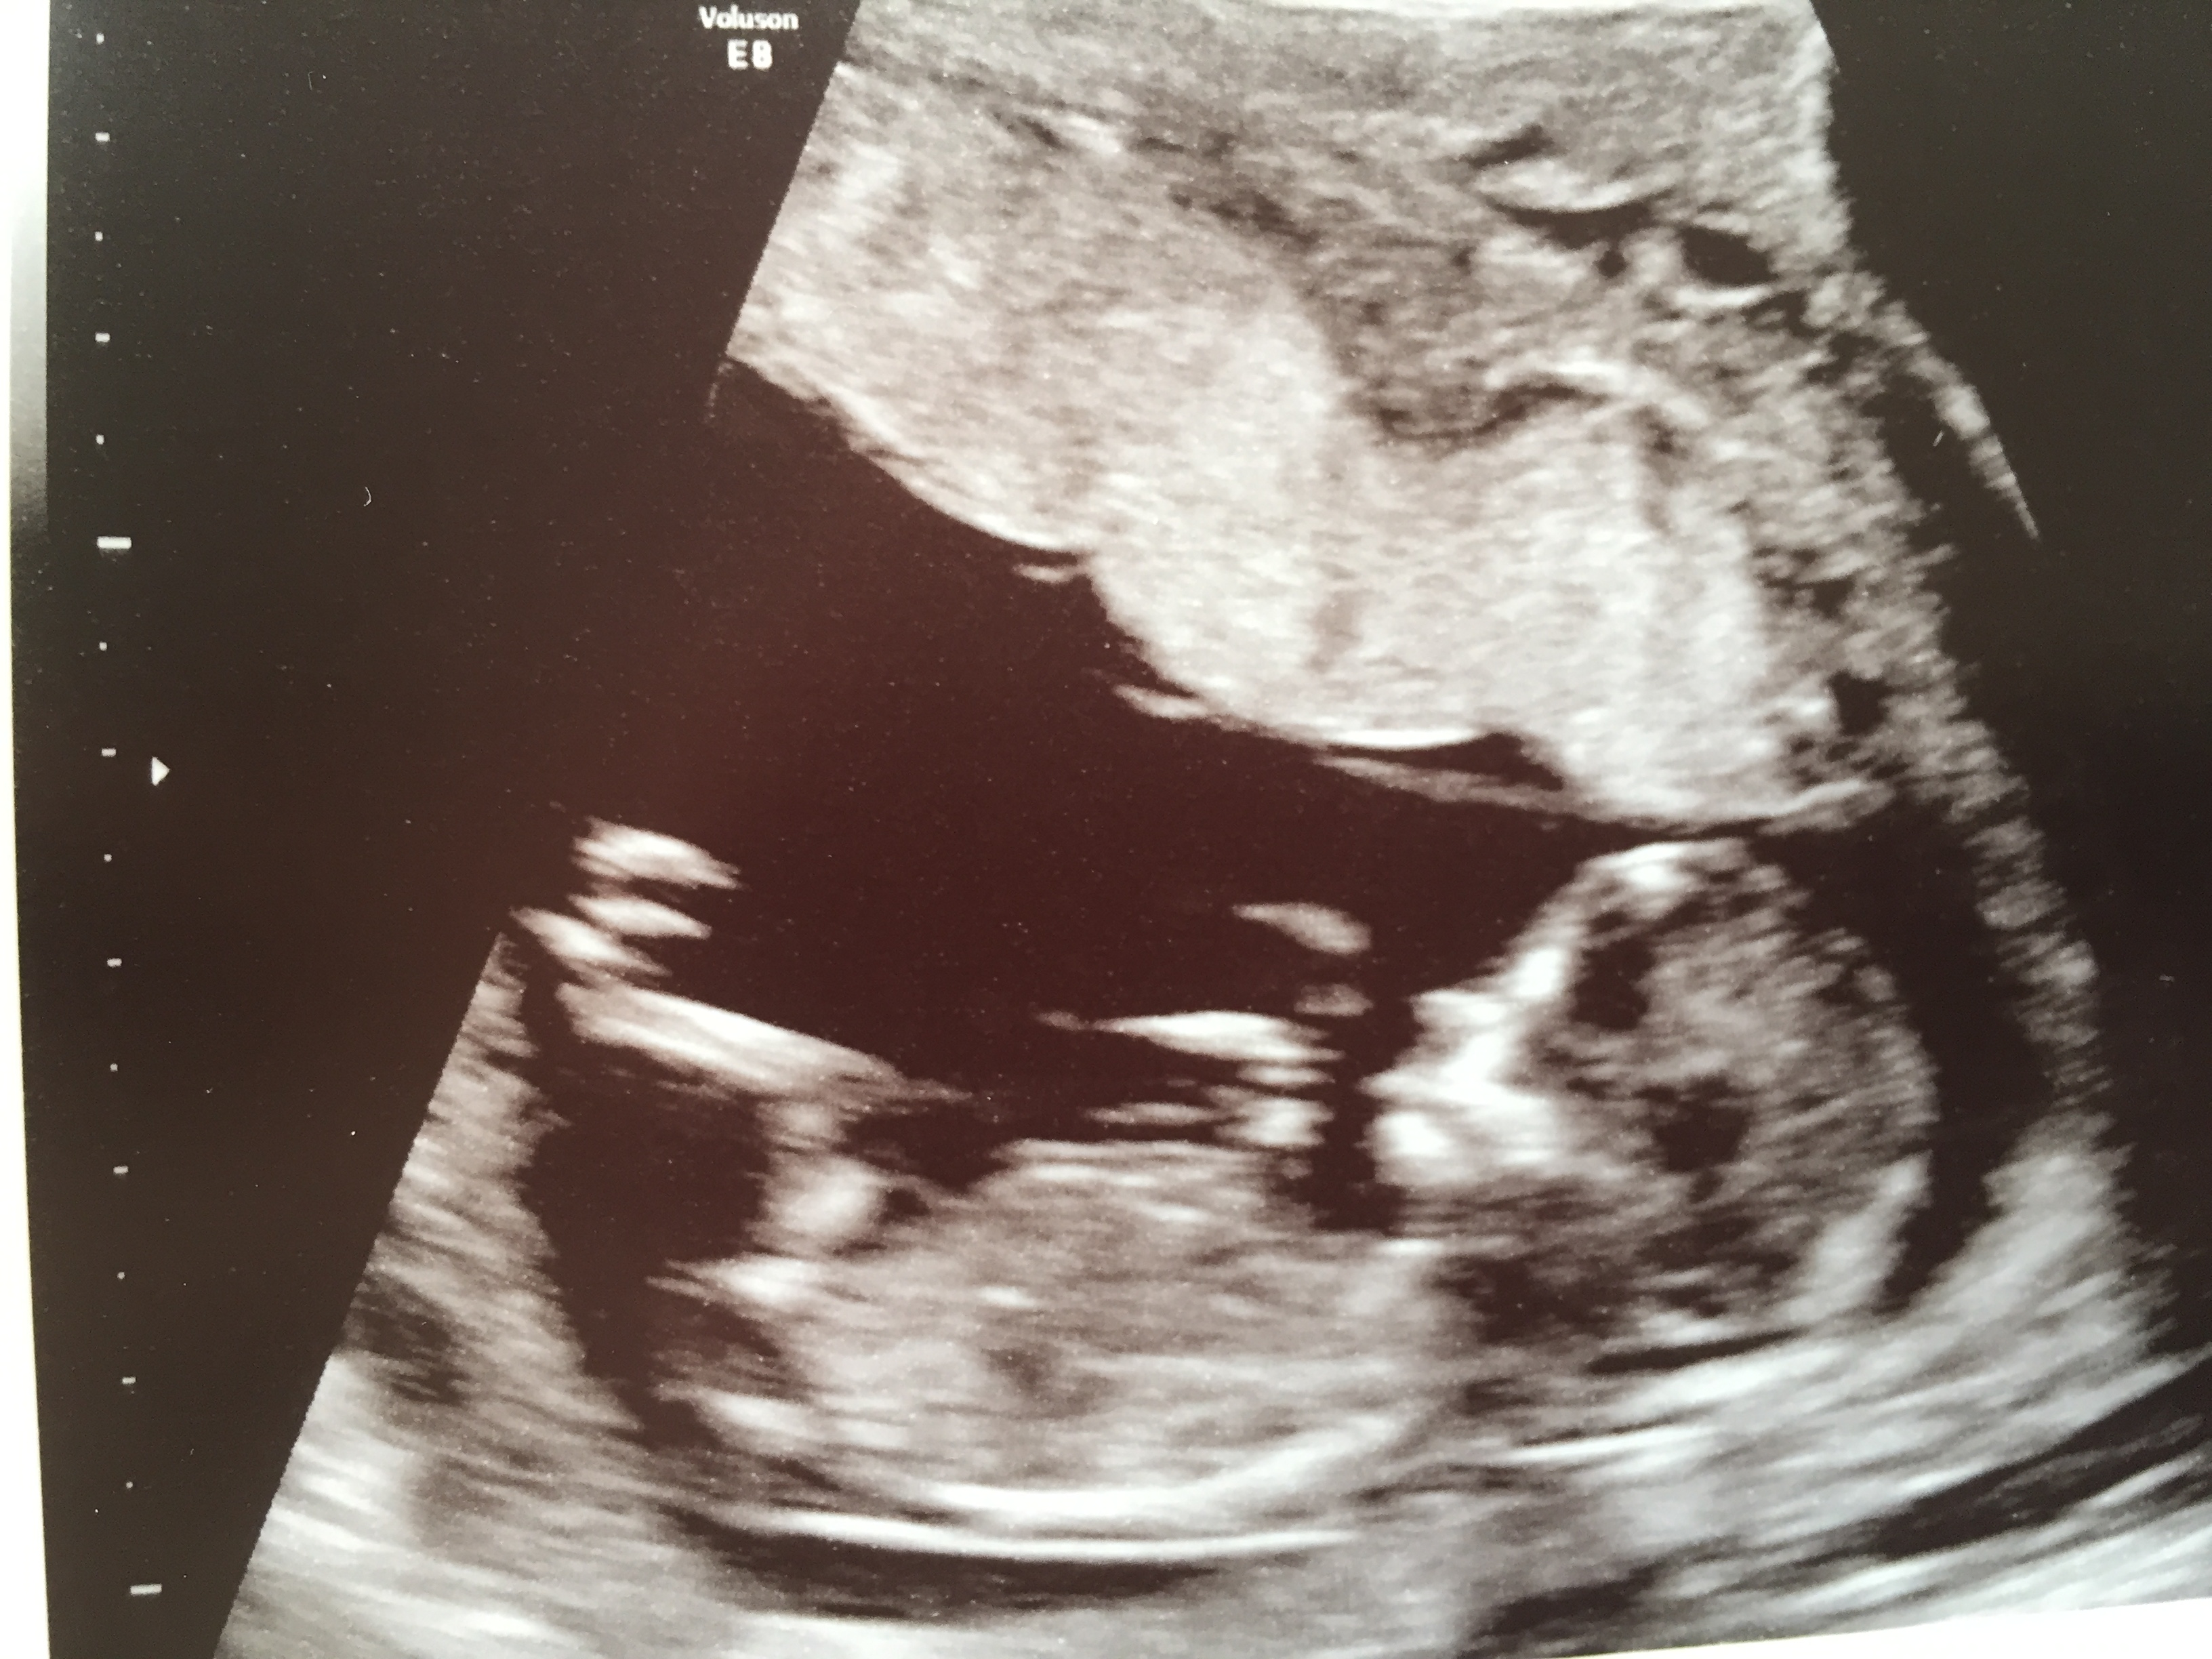

Hi everyone, I used to be on the forum a lot but had a miscarriage last November and since then have been fairly quiet. I am now 13+1 (that's what baby measured) and would love to know your guesses. Thanks everyone xxx

Not sure if these are any better. Any guesses anyone?

Oh my goodness, thank you for your guesses atomic and ksmom!! I would be beyond delighted if you were right!! I just can't decide myself, at the time the nub looked long and flat but one of the pics is troubling me cos it looks a bit pointed! My ds2 was more pointed at this point but I guess we will see! Thanks so much for your guesses! Anyone else like to look?